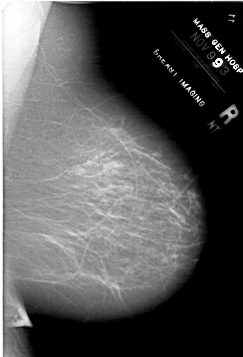

A_1768_1.RIGHT_MLO

RIGHT_MLO LINES 6421 PIXELS_PER_LINE 4366 BITS_PER_PIXEL 12 RESOLUTION 43.5 NON_OVERLAY